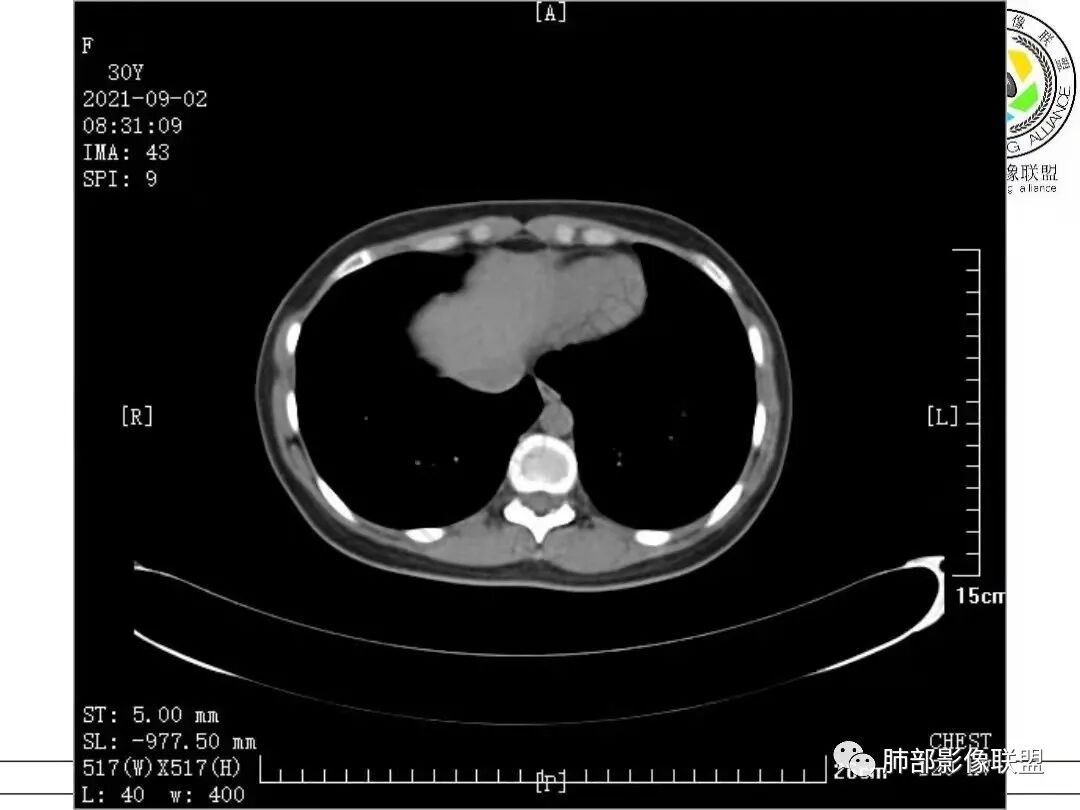

1.病例一:68岁男性,体检发现肺结节,肿瘤标志物CA199、CA50、CEA升高,其中CEA升高显著,超过正常范围的5倍以上。右肺下叶胸膜下结节影,整体较膨隆,部分层面可见锯齿状边缘,边界清晰,周围可见细毛细影,可见血管集束征、胸膜牵拉。密度不均,可见磨玻璃密度区及空泡征,胸膜下脂肪间隙显示不清。增强后显示轻、中度强化。